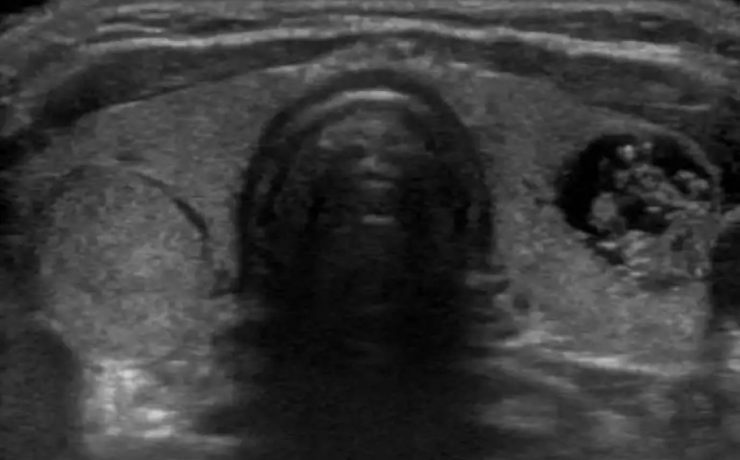

TÉCNICA ULTRASONOGRÁFICA DE PRÓSTATA: Los aparatos de ecografia suelen tener sondas transrectales diseñadas para la ecografia del recto y de la próstata. Las sondas deben ser de al menos 5 MHz y la mayoria son de 7 u 8 MHz. Se utiliza el transductor de vision terminal que permite imagen